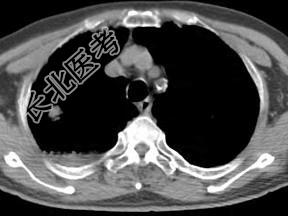

- 单项选择题男,76岁, 气喘数年,胸痛一月余, 结合影像图像,选择最可能的诊断 ( )

A、右上肺结核球

B、肺间质纤维化

C、右上肺瘢痕癌

D、右上肺错构瘤

E、右上肺肉瘤